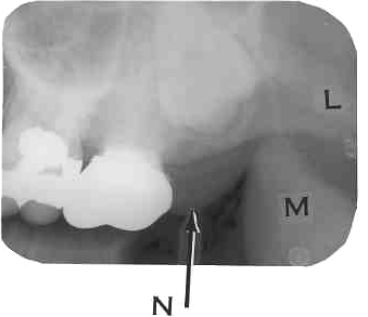

24. What is showing by N?

25. What is shown by M?

26. What is shown by L?